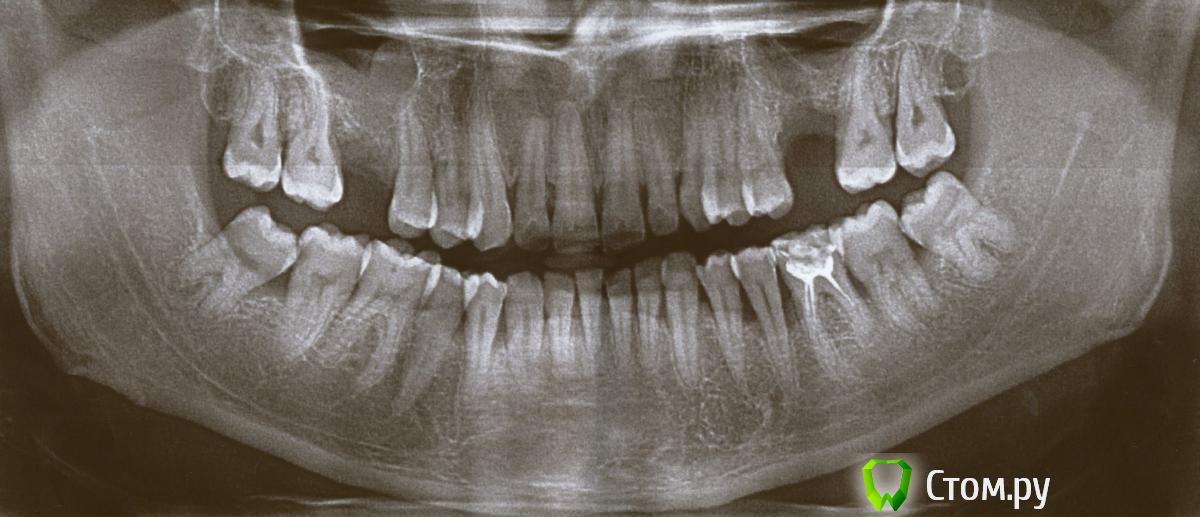

Алексей Александрович Опубликовано 11 апреля, 2014 Автор Поделиться Опубликовано 11 апреля, 2014 Вот мне ответил профессионал. Можете чо-нибудь добавить или наоборот раскритиковать?Добрый день.Характер резорбции костной ткани говорил о воспалительной причине, т.е. это пародонтИТ.И, кстати, нижний зуб слева на снимке - у него на верхушке корня есть небольшая киста, зуб требует депульпирования и лечения периодонтита.В прикрепленном файле ваш снимок с пометками:слева внизу указан зуб с периодонтитом (писал о нем выше). Остальные отметки показывают основные проблемные участки, где у зубов есть глубокие пародонтальные карманы. В области передних верхних зубов резорбция кости есть везде, но особенно в области 1 зуба. Внизу степень резорбции кости также неоднородна - преимущественно в области 4-5х зубов слева и справа.Самые большие изменения у зуба, о котором вы пишите (этот зуб отмечен черный стрелкой). Белые линии отмечают уровни до которых рассосалась кость.Нужен хороший пародонтолог. И тут нужно не только снимать качественно поддесневые зубные камни и проводить противовоспалительную терапию, но и нужно делать открытый кюретаж с подсадкой синтетической костной ткани особенно в области нижних зубов (не всех, а некоторых групп зубов). А также срочно депульпировать нижний резец и шинировать его к нескольким соседним зубам стекловолокном).По вашим назначениям я уже вижу полный непрофессионализм врача. Депульпирование пародонтитных зубов делается в случаях, если атрофия костной ткани больше 1/2 длины корня, у вас у нижнего резца резорбция (атрофия) значительно больше. Кроме того, лазер будет только способствовать увеличению скорости резорбции кости, т.к. при таком лечении вся причинная инфекция как была так и останется на своих местах, только немного станет по-меньше. Лечебные инъекции - это судя по всему уколы Линкомицина... А вот это уже серьезно. Серьезный вред может нанести.Уколы антибиотиков должны быть только внутримышечно либо в таблетках."повязка для нагноившегося кармана" - такой же бред.Лечение должно было быть примерно таким (основные моменты):1. Снятие наиболее массивных зубных отложений в 1ое посещение, промывание карманов, обработка десны гелем. Назначение 10ти дневного курса антибиотикотерапии, антисептических полосканий, и противовоспалительного геля для обработки десны.Депульпирование нижнего резца (в канале оставить лекарство, зуб сразу пломбировать нельзя).2ое посещение - продолжение снятия зубных отложений (в том числе поддесневых), промывание карманов, обучение правильной гигиене полости рта. Промывание корневого канала нижнего резца, смена лекарста.Далее - через несколько дней, когда десна успокоится, уменьшится ее отек - полировка поверхности корней в пародонтальных карманах и коронок всех зубов. Пломбирование корневого канала нижнего резца. Далее пациент сам продолжает делать все назначения.Далее - после полного стихания воспаления (через 10-12 дней) решается вопрос о необходимости чистки пародонтальных карманов от грануляций, т.е. о необходимости Открытого кюретажа. У вас это происходит особенно в области 4-5х зубов внизу и боковом резце вверху.Шинирование нижнего резца обязательно, или вы его очень быстро потеряете. Кости очень мало, зуб не держит нормально жевательную нагрузку - мигом расшатается и выпадет иначе. Ссылка на комментарий